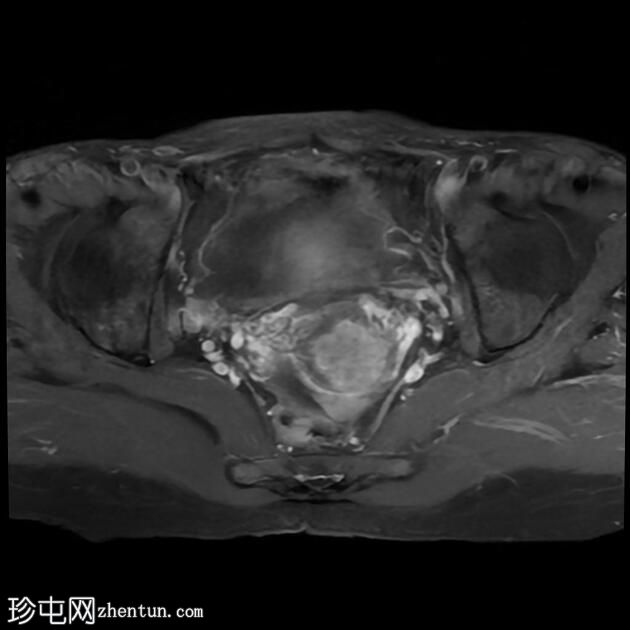

该宫颈癌体积较大,局部晚期,大小为22 x 40 x 42 mm,起源于宫颈左后外侧壁,向下延伸至阴道上三分之一处,位于宫颈中后外侧壁。

病变还累及左侧前外侧的宫旁组织。